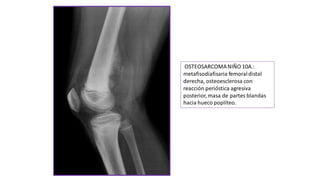

OSTEOSARCOMANIÑO 10A.:

metafisodiafisaria femoraldistal

derecha, osteoesclerosa con

reacción perióstica agresiva

posterior, masa de partes blandas

hacia hueco poplíteo.